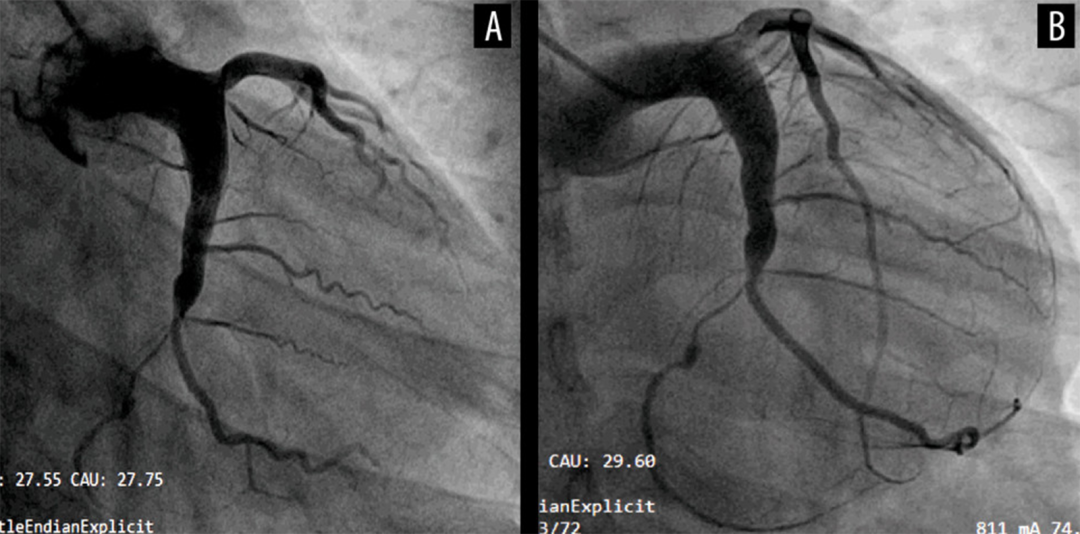

冠脉扩张症定义为弥漫性扩张累及范围超过其长度的1/3以上,且扩张段的直径是相邻正常段直径的1.5倍以上。这与冠脉瘤的定义不同,后者是指冠脉某段直径超过相邻正常冠脉段直径的1.5倍,且累及范围占总长度的1/3以下。冠脉扩张症有时会导致急性冠脉综合征。研究显示,扩张段存在明显的血流缓慢现象,可能导致缺血和血栓形成。近期,天津医大总医院李永乐教授团队在《American Journal of Case Reports》报道了一份特殊病例“Recurrent Acute Myocardial Infarction in a Patient with Severe Coronary Artery Ectasia Followed Up for 10 Years: Implications of Anticoagulant Therapy”,报告了一例在9年间因同一冠脉扩张病变部位局部血栓形成导致再发心肌梗死的病例,并讨论了长期抗凝治疗的有效性。